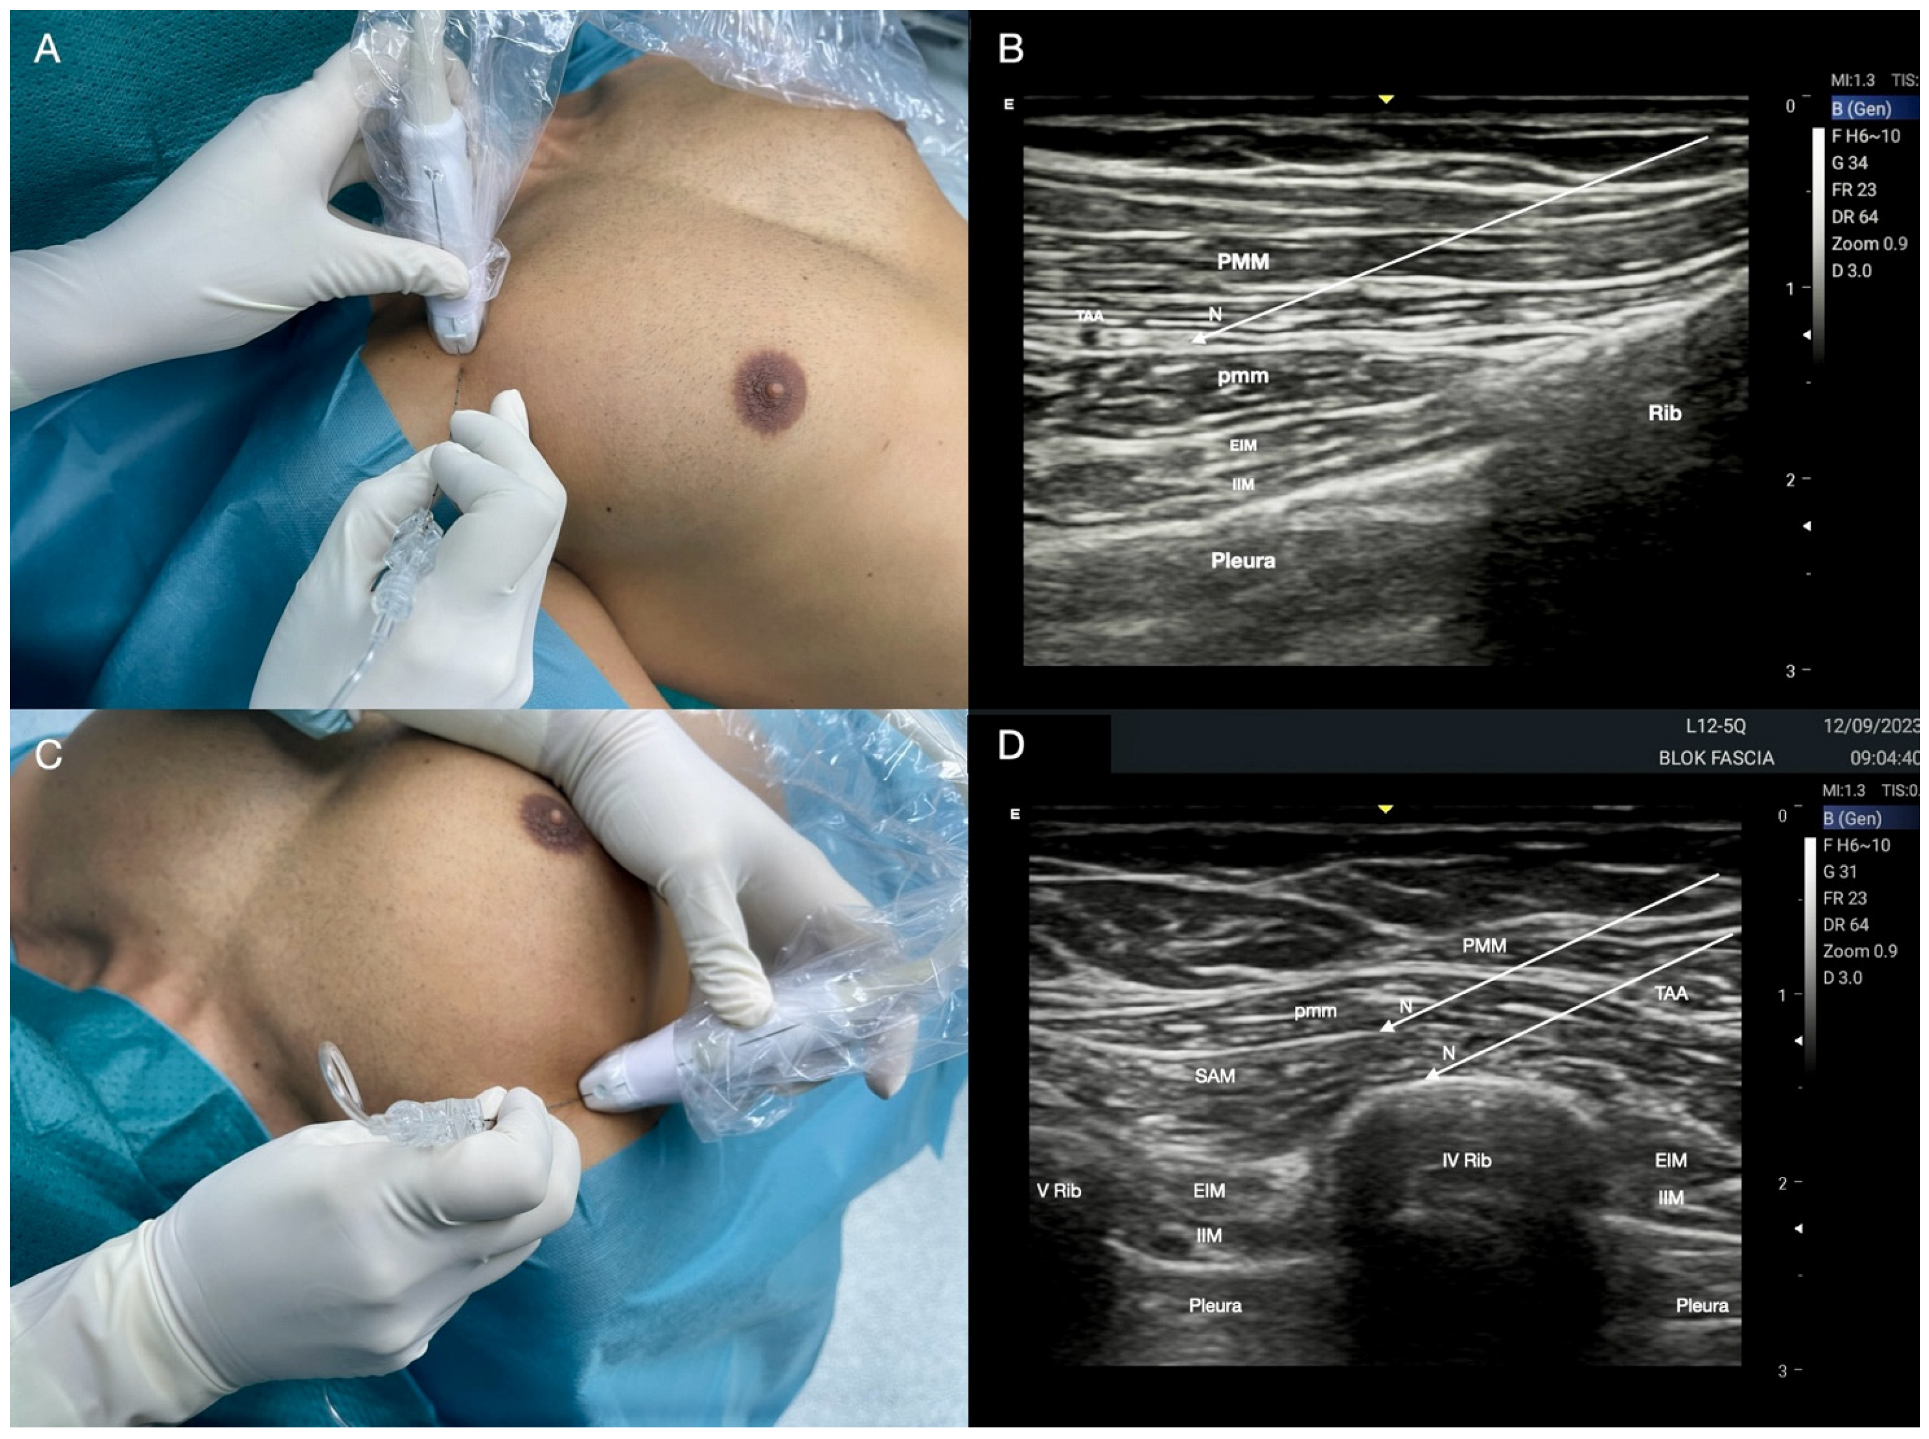

2.3. Interpectoral Plane Block (IPP) and Pectoserratus Plane Block (PSP)

Technique for IPP and PSP

| IPP | Postoperative sternal analgesia, placement of anterior chest drains, post-traumatic chest injuries, ICD or pacemaker implant. | Lateral and medial pectoral nerves. Pectoral muscles. Anterior thoracic wall. Between pectoralis major and minor muscles. 10 mL of LA. | The lateral to medial approach allows a more comfortable position than the medial to lateral one. The pectoral branch of the thoraco-acromial artery is an important landmark to identify the inter-fascial plane. An effective block is realized when the ultrasound “double V” sign is visualized. |

| PSP | Pain management after thoracotomy in association with SAP block. | T2–T6 intercostal nerves lateral cutaneous branches. Lateral thoracic wall. Intercosto-brachial, thoracic longus and thoraco-dorsal nerves. 4th rib. 20 mL of LA. | Opposite decubitus to the surgical site; probe placed on the mid-axillary line. At level of 4th rib, the LA can be injected below the plane of serratus muscle realizing a deep SAP block or blocking the branches of intercostal nerves in the middle axillary line. |